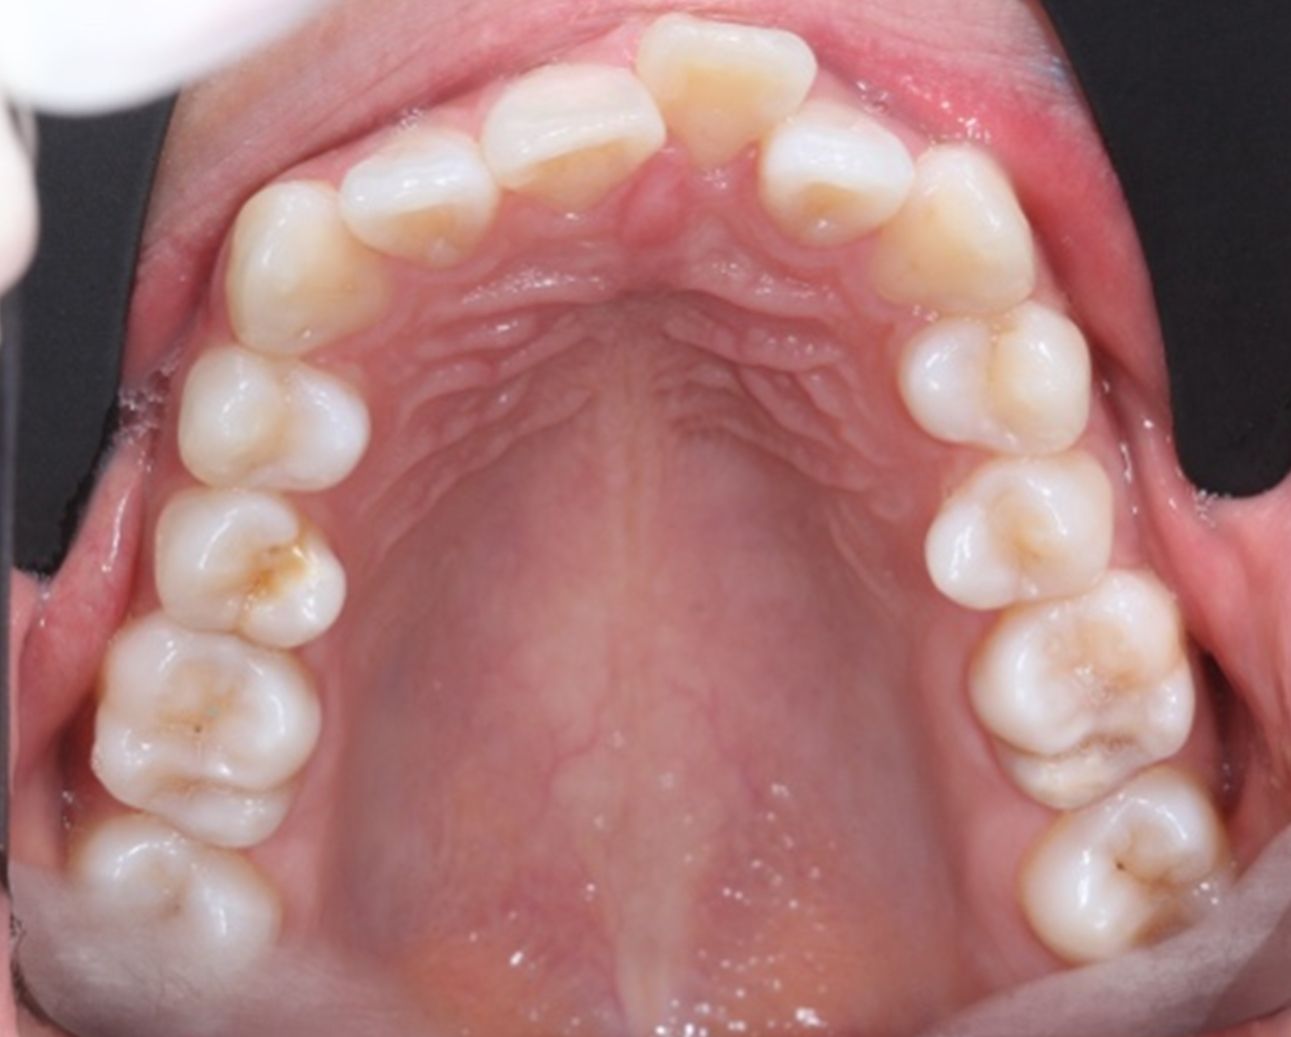

A continuación, mostramos el caso de una paciente adulta con clase II ósea y dentaria.

Con Ortodoncia Invisible, y gracias a la cooperación de la paciente, conseguimos este resultado y, lo más importante de todo, que la paciente sonría sin complejos.